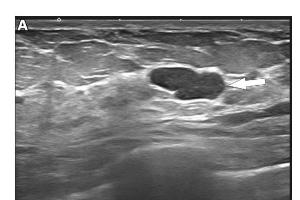

医疗科研新动态 | 菁易科研解析乳腺超声在乳腺疾病诊疗中的前沿进展

综述乳腺超声技术现状及临床应用,探讨新兴技术潜力,提升诊疗水平。